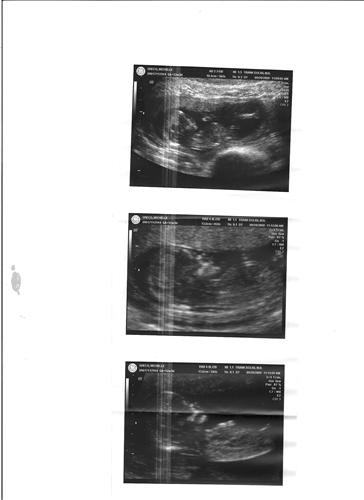

sono12w3d

CoutureMaMa

9/28/09